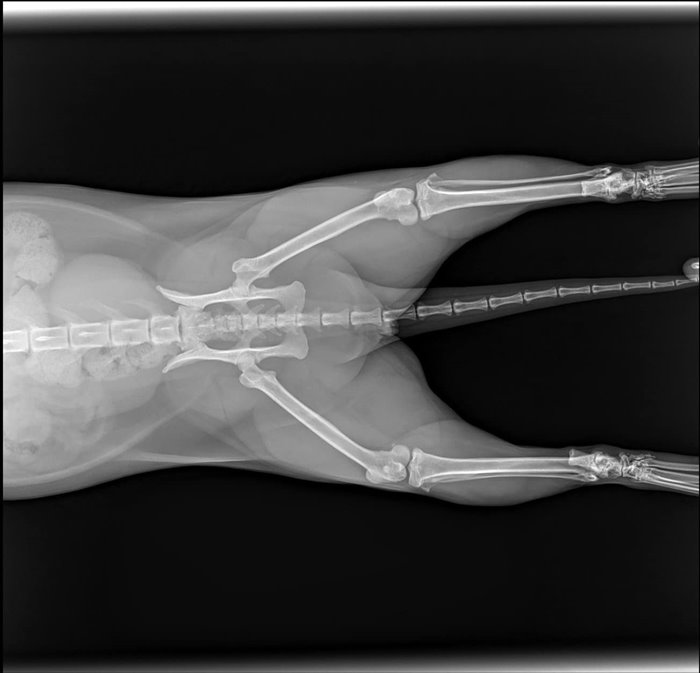

วันที่ 28 พฤษภาคม 2566 สรยุทธ สุทัศนะจินดา รายงานว่า ได้มีการอัปเดตอาการ น้องซิฟู เหมียวน้อยตัวดังกล่าวว่า "อัปเดตอาการน้องซิฟู หรืออาจารย์ซิฟู ในกังฟูแพนด้านั่นเอง น้องปกติทุกอย่าง กินข้าวได้ อึขับถ่ายปกติ ไม่มีอาการบวมหรือช้ำในใด ๆ มีเพียงแค่เล็บหลุด 2 นิ้ว และเป็นห้อเลือดเท่านั้นครับ"